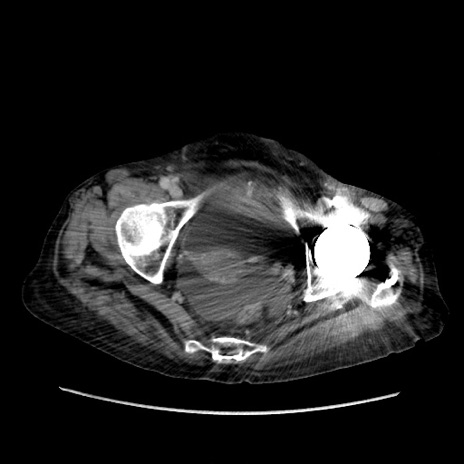

症例31(横断像)

【症例】80歳代 女性

【主訴】腹部膨満感

【現病歴】他院にて肝硬変にてフォロー中。1週間前から便秘、腹部膨満感、臍部腫瘤あり受診となる。

【既往歴】肝硬変

【身体所見】腹部膨隆あり、皮膚変化なし、疼痛なし。

【データ】WBC 4600、CRP 0.25